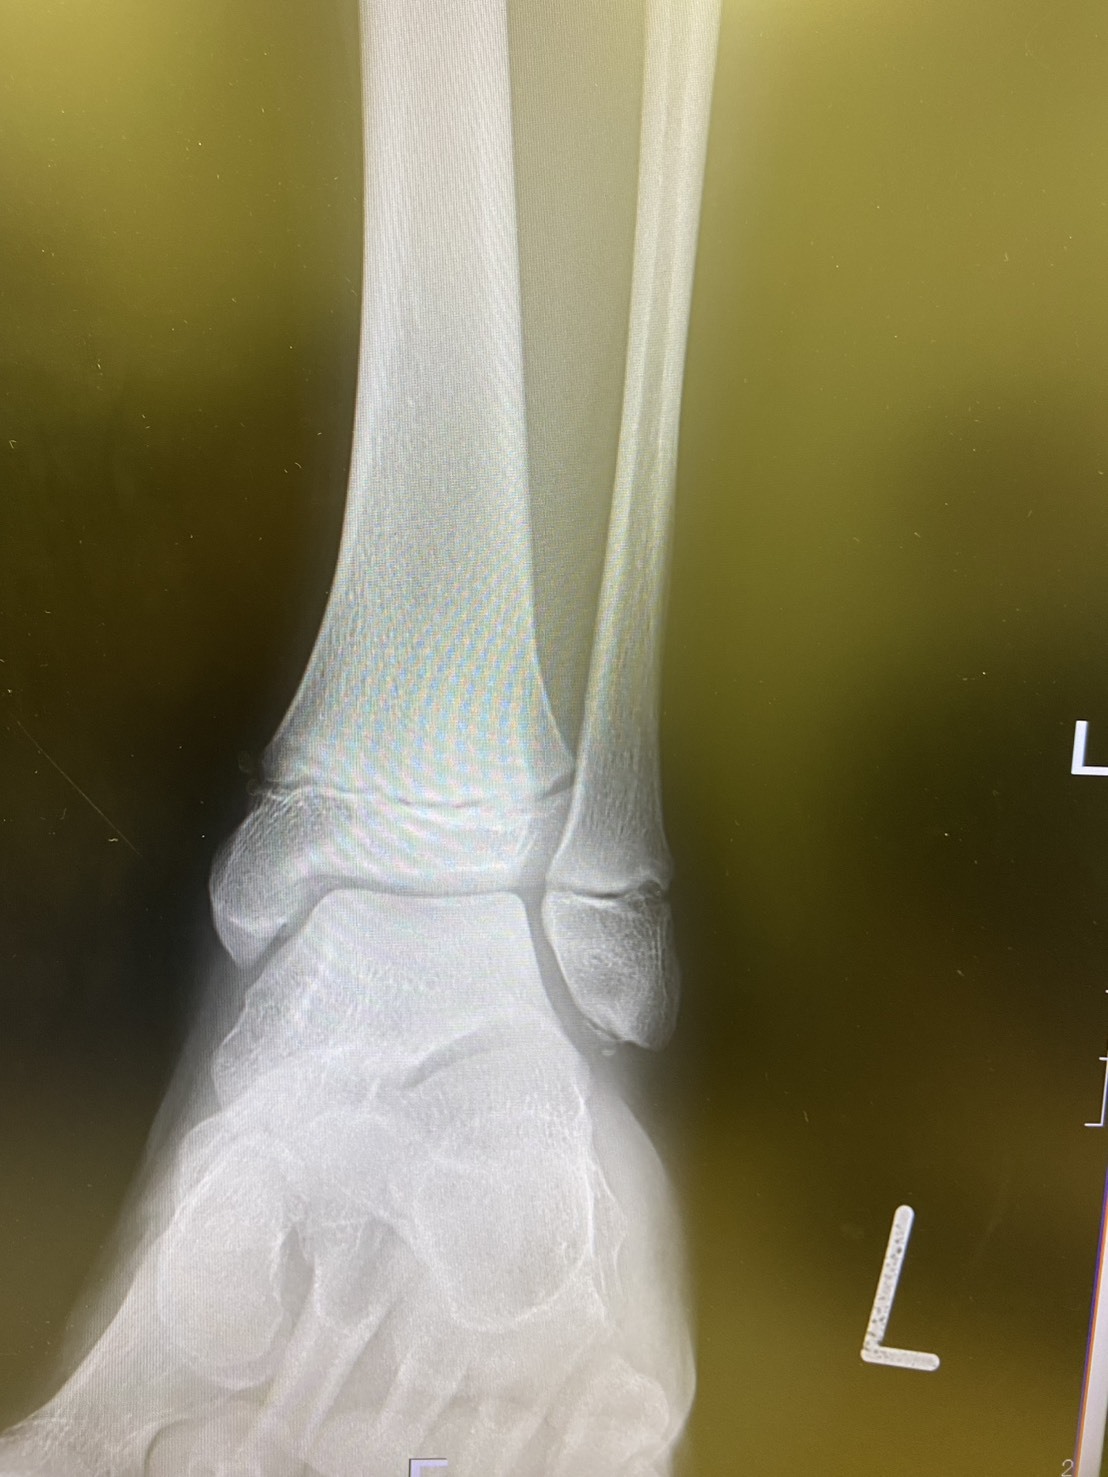

左腓骨骨端線から近位にかけての圧痛を認め

歩行時痛(++)内反ストレステスト(+)

骨折を伴う骨端線損傷と判断し

近隣整形外科に対診。

結果、予想通り骨折と診断。